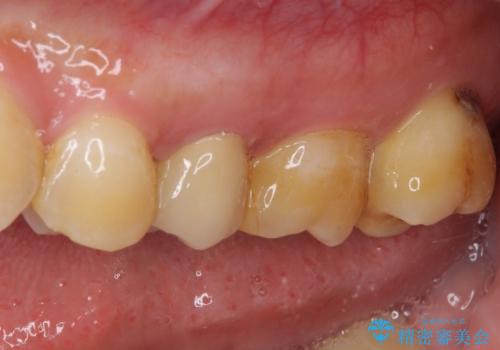

来院されたときには、神経を全て取り除くことになるであろうと思っていらっしゃいましたが、結果としては歯根部分の歯髄を残すことができました。

神経組織を全部または部分的に除去することが分かっていたため、ラバーダムなどの環境を整え、無菌的環境下にて処置を進めて行きました。

虫歯は深くまで進行しており、歯冠部の神経から出血が認められました。神経を部分的に除去したところ出血が治まったので、生体親和性の非常に高いセメントにて充填し、仮封をしました。

後日状態を確認したところ、残された神経に異常は認められませんでした。

欠損歯質は比較的小さかったため、セラミックインレーにて修復治療を行いました。